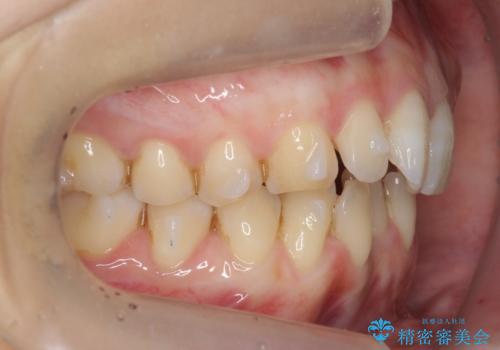

前歯のガタつき インビザラインで 下の前歯を1本抜歯

- 前歯のがたつきを主訴に来院。マウスピース矯正を希望されました。

治療にあたり、下の前歯を一本抜歯しています。

非抜歯で無理に治療をしようとすると、下の前歯の骨が薄く歯ぐきが下がったり、歯がぐらついたり、がたつきが完全にとれないリスクがあることを説明しました。

下の前歯が3本になるため、上下の正中は合わない仕上がりとなりますが、正中を合わせるには上下左右4本抜歯の上、ワイヤー矯正となってしまいます。

それよりは抜歯の数も少なく、メリットが大きいのではないかと説明し、選んでいただきました。

短期間できれいな歯並びになり、大変満足していただきました。